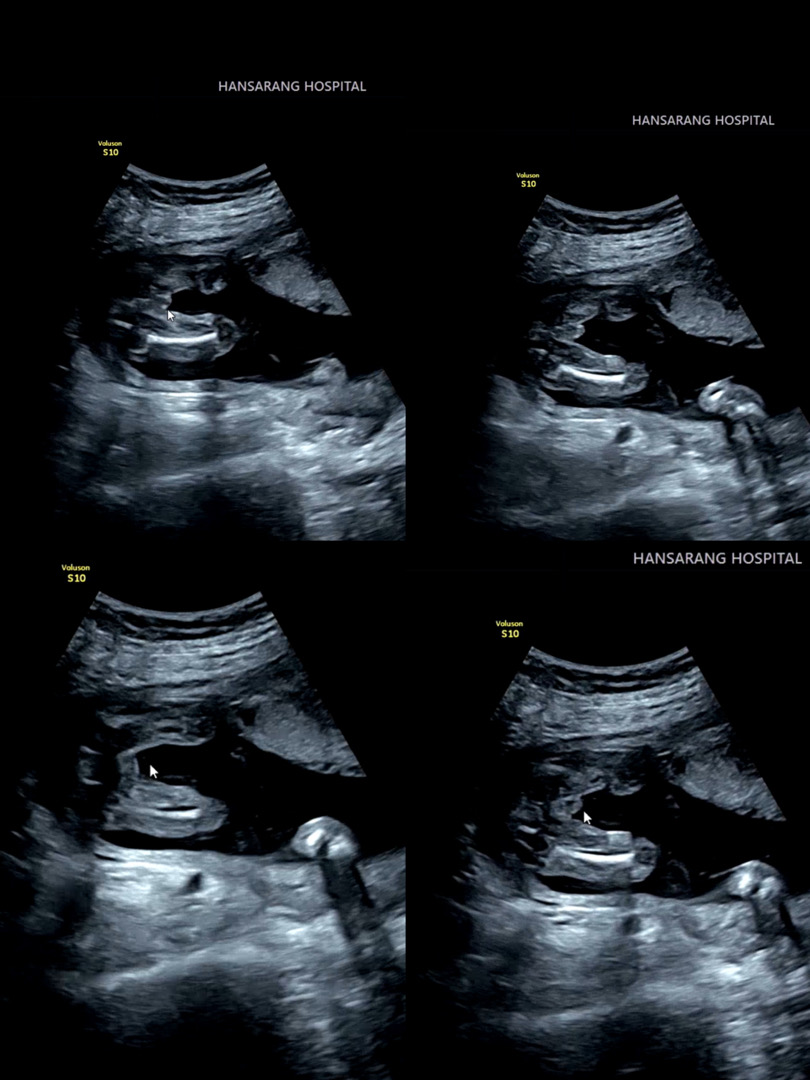

18주차 다리사이 🌶🍑 뭐 같나용..?

18 주차 초음파 보고왔는데 🌶같나용...? 🍑같나용..?

초음파 볼 때 마다 탯줄 감겨있어서 의사쌤두 긴가민가 하다고 하셔서 아직 확답을 못 들었어요 ㅜㅜ